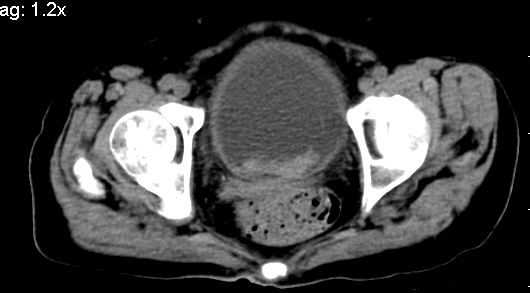

标题: CT10133:F、74岁,反复血尿10天。 [打印本页]

标题: CT10133:F、74岁,反复血尿10天。

考虑膀胱癌可能性大伴双侧输尿管下端扩张.

1.膀胱后壁见不规则致密影,占位?膀胱内凝血块?建议俯卧位扫描、膀胱镜检查.

2.双侧输尿管下段扩张.

1.膀胱后壁见不规则致密影,随体位改变,为膀胱内凝血块;

2.双侧输尿管下段扩张.输屎管结石可能大。建议作进一步检查。

双侧输尿管下端扩张,并膀胱内血凝块 输尿管下端结石